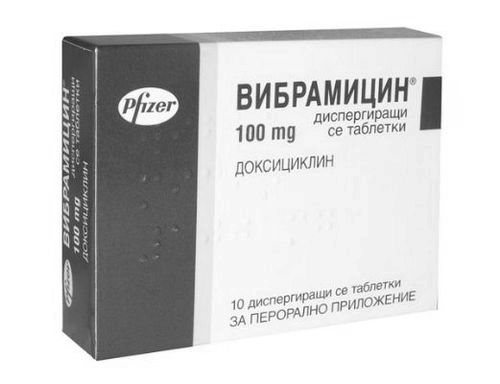

Вібраміцин

Антибіотик групи макролідів. Призначається в разі стабільного перебігу хвороби. Застосування даної групи ліків має бути погоджено з педіатром. Препарат сильний, він усуває бактерії, які викликали захворювання.